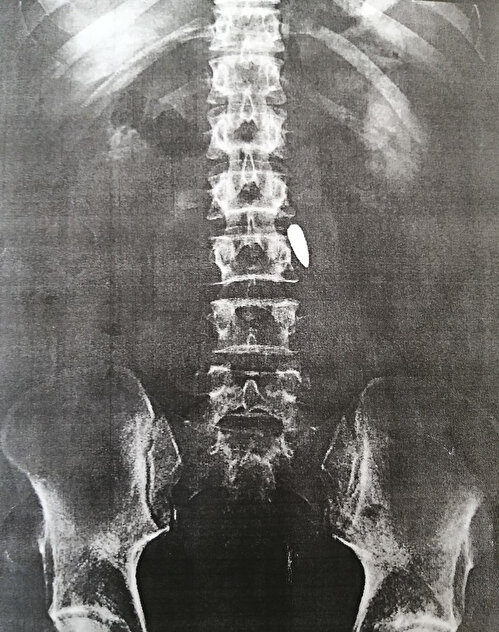

Onur Can Kuş, bu sırada hainlerin ateşlediği bir merminin beline isabet etmesi sonucu yaralandı. Yaralanan genç, orada bulunan sivil bir vatandaşın motosikletiyle Haydarpaşa Numune Eğitim ve Araştırma Hastanesi’ne kaldırıldı. Kuş, burada hemen ameliyata alınırken, omuriliğinin hemen yanına saplanan kurşun, yüksek hayati risk nedeniyle çıkarılamadı.

"Yüksek hayati risk nedeniyle kurşun çıkarılamadı"